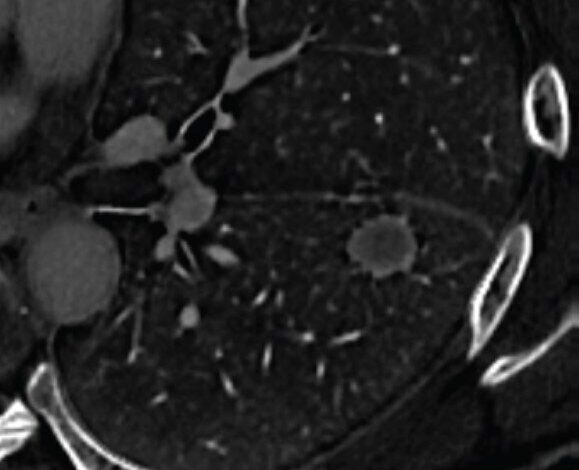

DECT multifásico com contraste de tórax realizado para planejamento cirúrgico. A imagem axial do mapa de concentração de iodo, reconstruída a partir da aquisição da fase de equilíbrio, mostra alta concentração de iodo periférica em forma de anel fino, envolvendo toda a circunferência do nódulo. Nódulo foi submetido à ressecção, revelando metástase de carcinoma de orofaringe. O caso representa um exemplo verdadeiro positivo do uso de alta concentração periférica de iodo em forma de anel para o diagnóstico de metástase pulmonar. Crédito: ARRS/AJR

De acordo com um manuscrito aceito publicado no Jornal Americano de Roentgenologiaos mapas periféricos de alta concentração de iodo em forma de anel da TC de dupla energia (DECT) podem ajudar a orientar o manejo em pacientes com câncer de pulmão conhecido e um nódulo solitário indeterminado.

Por fim, a alta concentração periférica de iodo em forma de anel no DECT mostrou excelente concordância interobservador (κ = 0,80) e teve sensibilidade de 52% e especificidade de 81% para diferenciar metástases pulmonares de cânceres pulmonares primários. Além disso, o achado previu independentemente a metástase pulmonar na análise multivariada [OR=7.81, 95% CI: 2.28–29.60; p=.001] combinando as características do paciente e da lesão.